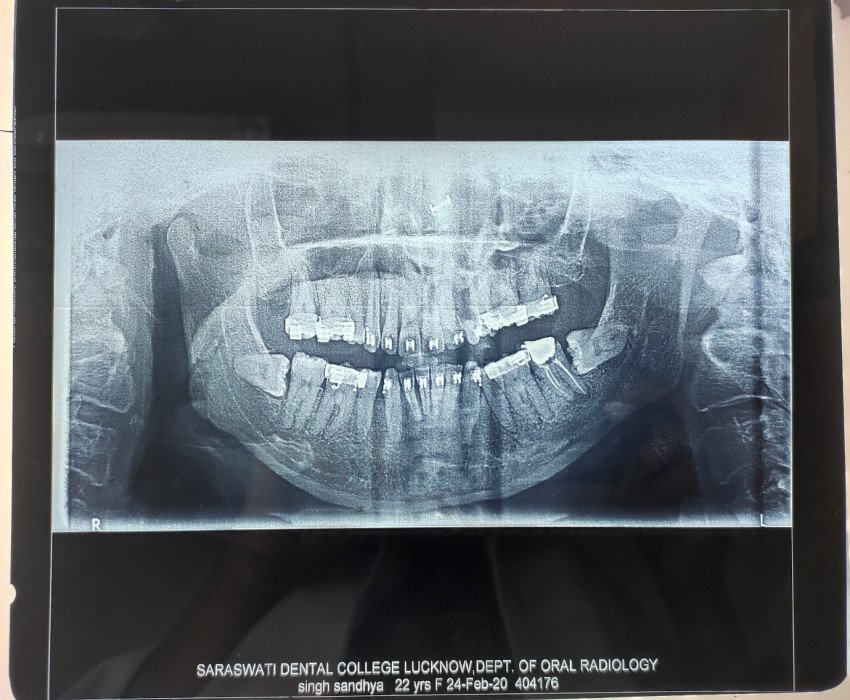

Orthognathic surgery may help to correct problems with swallowing or speech, correct bite fit or jaw closure issues, correct facial asymmetry, relieve pain caused by temporomandibular joint (TMJ) disorder, repair facial injury or birth defects and provide relief for obstructive sleep apnoea.

Surgery on the upper jaw may be performed to correct receded or protruding upper jaw, crossbite, abnormal teeth display during smile, open bite or reduced growth of the middle of the face. Whereas, the surgery on the lower jaw may be performed to correct a receding or protruding lower jaw and to correct any chin deformity.

Orthodontists work hand in hand with oral and maxillofacial surgeons and through the surgery, it is possible to place the teeth and jaws in a more attractive, functional, and healthy position.